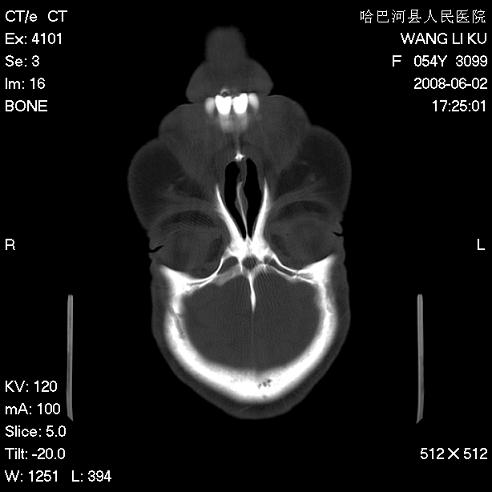

标题: CT13803:反复性鼻塞、流涕一年余 [打印本页]

标题: CT13803:反复性鼻塞、流涕一年余

副鼻窦炎,右上额窦积脓。左眼肌锥内见致密影,视神經受压

1.全组副鼻窦炎2.双侧上颌窦积液

全组副鼻窦炎

1)全副鼻窦炎(左侧上颌窦黏膜下囊肿或息肉)。2)左眼眶肌锥内不规则小结节状软组织密度影;考虑为小血管瘤可能。建议行ct增强扫描检查。

全组副鼻窦炎,左侧肌锥内不规则形软组织肿块影,与眼外肌密度相当,左侧视神经受压,肿块与视神经及眼外肌分界清晰,眼外肌无增粗,眶壁无破坏,球后脂肪间隙不模糊,考虑良性改变,小血管瘤或神经源性肿瘤可能,建议增强扫描。

谢谢,增强扫描做了,眶内病灶与海绵窦同步明显强化,血管瘤